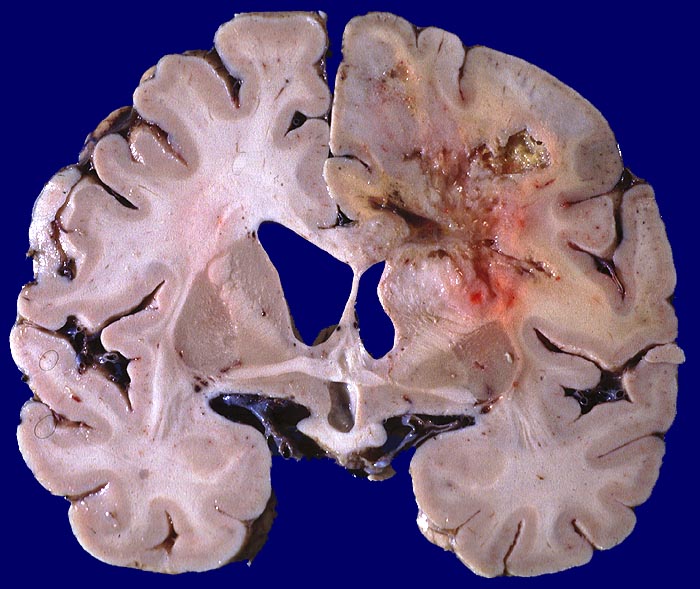

Morphologie:

Die Schnittfläche ist auffallend bunt. Dies ist bedingt durch ein Nebeneinander von graurotem vitalem Tumorgewebe, gelben Nekrosen, roten Einblutungen und gelegentlich grünlichen Gallertzysten.